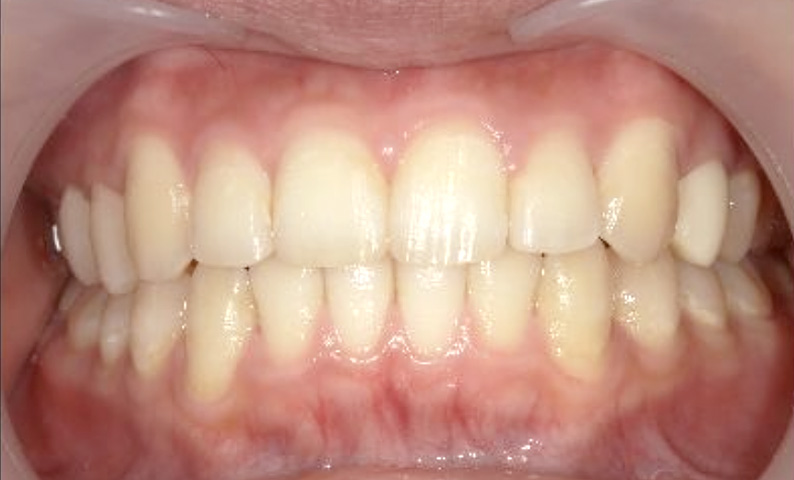

症例_025 上下顎の部分矯正

治療期間:13ヶ月金額:51万円+税女性前歯のガタガタ出っ歯

| Before | After |

|---|---|